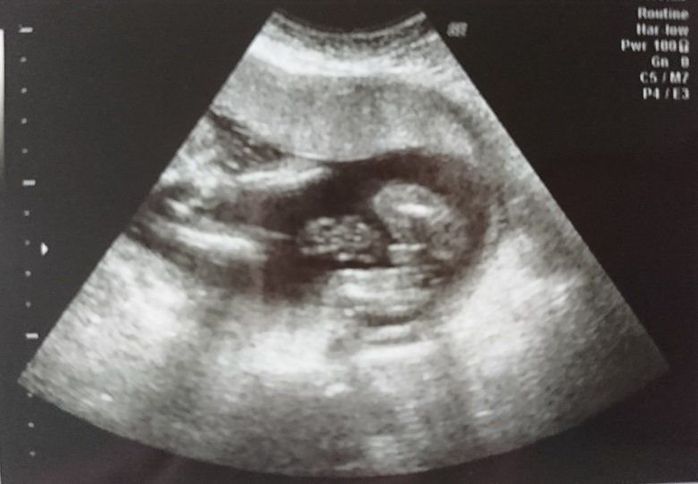

妊娠33週目のエコー写真

おなかが大きくなり、胃を圧迫してあまり食べられなくなってきました。大きなおなかでの通勤はかなり厳しく、産休に入るのを指折り数えていた日々でした。電車で席を譲ってもらえたり、会社で周囲の人が気遣ってくれたのがとても嬉しく、人の温かさに救われていた時期でした。夜中におなかの中で動き回るので、寝不足になっていた時期です。赤ちゃんの推定体重は2213gでした。